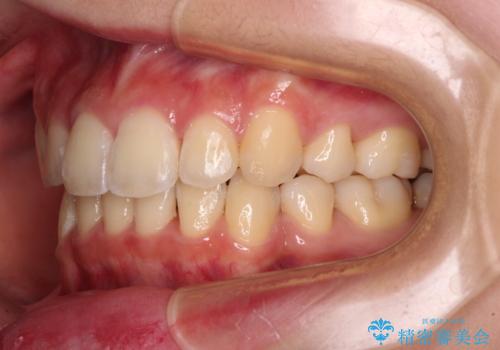

上下左右4本抜歯する場合には、通常2年から2年半ほどの期間を要しますが、僅か1年半で終了することができました。

- 口元の閉じにくさを気にして来院された患者様です。

上下ともに歯列が前方に突出していたため、上下左右の第一小臼歯4本を抜去し、ワイヤー装置による矯正治療を行うこととしました。